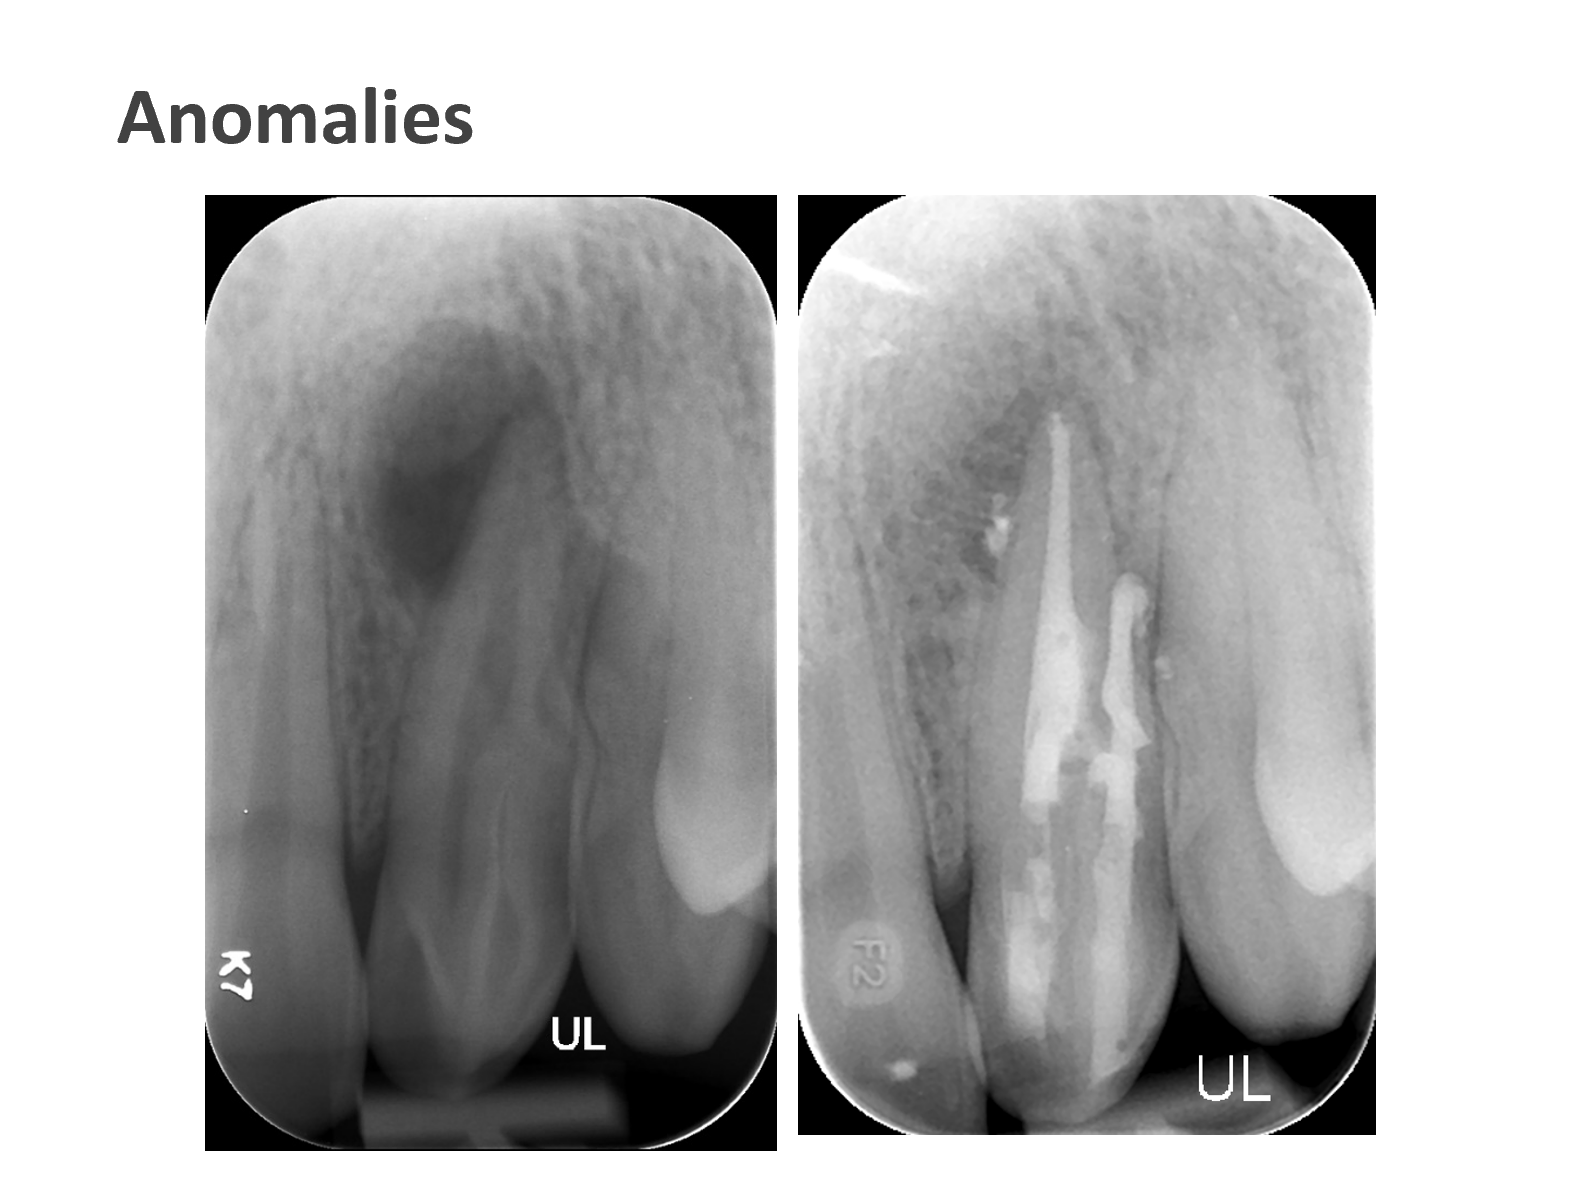

We take pride in providing the highest standard of care at ICE and believe that only the best is good enough for our patients. As such, Shakil completes all endodontic procedures using a state-of-the-art dental microscope. We accept referrals for consultations, root canal treatment (primary and retreatment), management of endodontic emergencies, dentoalveolar trauma and we are also happy to provide definitive restorations as required.